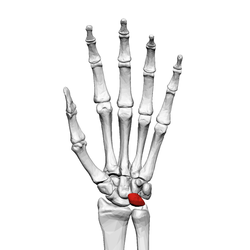

![]() Left hand anterior view (palmar view). Lunate bone shown in red. | |

The lunate bone (semilunar bone) is a carpal bone in the human hand. It is distinguished by its deep concavity and crescentic outline. It is situated in the center of the proximal row carpal bones, which lie between the ulna and radius and the hand. The lunate carpal bone is situated between the lateral scaphoid bone and medial triquetral bone.

The lunate is a crescent-shaped carpal bone found within the hand. The lunate is found within the proximal row of carpal bones. Proximally, it abuts the radius. Laterally, it articulates with the scaphoid, medially with the triquetral, and distally with the capitate. The lunate also articulates on its distal and medial surface with the hamate bone.[1]:708[2]